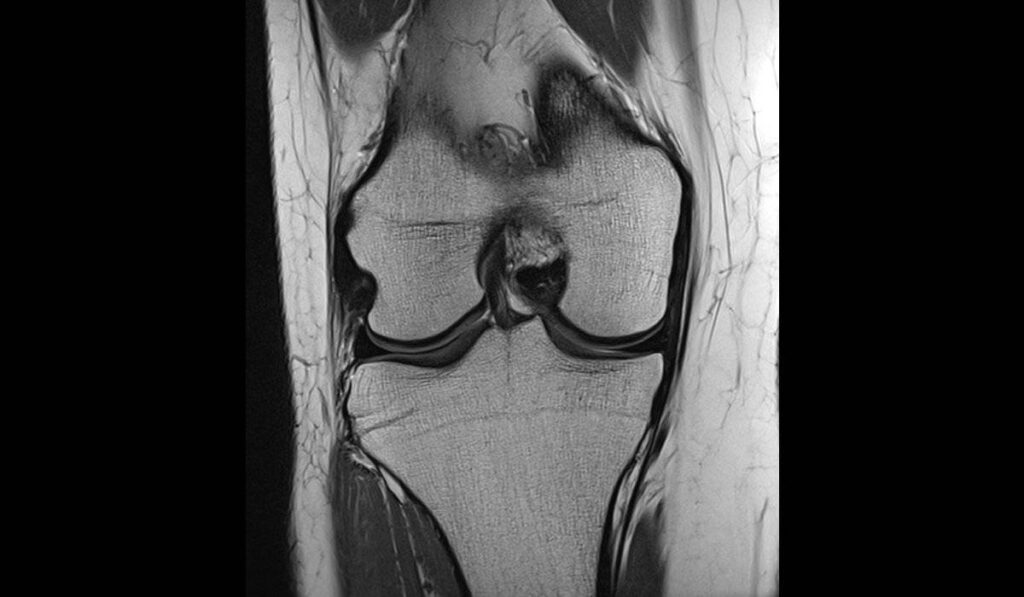

Bildgebung

Eine anschließende Röntgenuntersuchung kann allein nicht dabei helfen, die Diagnose zu sichern. Mit dieser Untersuchung lassen sich jedoch zusätzliche knöcherne Verletzungen im Bereich des Knies oder knöcherne Bandausrisse feststellen.

Um den Kreuzbandriss darzustellen, benötigt man eine MRT Untersuchung. Nur anhand dieses Verfahrens lässt sich klar feststellen, ob ein Kreuzband ein- oder sogar vollständig gerissen ist.

Beide Untersuchungen geben zusammenfassend also Aufschluss über den Schaden an sich, sowie eventuelle zusätzliche Verletzungen der Seitenbänder, der Menisken, des Gelenkknorpels, als auch des Knochens.